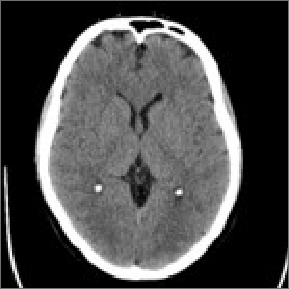

Images are collected during your DBS procedure.

Collected images are evaluated to see the exact location of your leads.

The images are loaded into the programming software and therapy is programmed precisely – based on the location of your leads.

Stimulation can be adjusted to minimize side affects, at the initial programming and in the future.